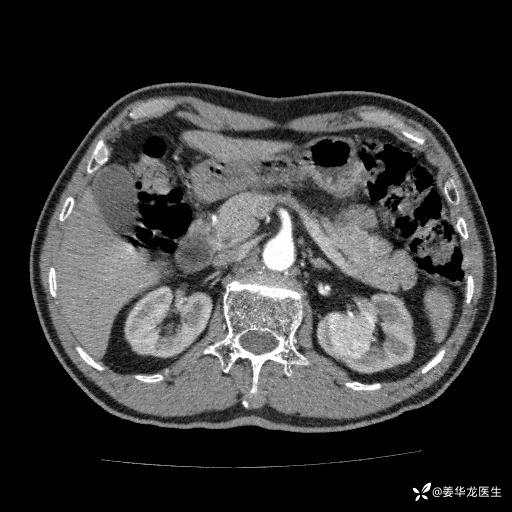

左肾中心型肾门部肿瘤39mm×34mm×36mm,右肾GFR25ml/min,部分切还是全切?

患者75岁老年男性,体重50kg,无高血压、肾病、糖尿病等基础病,检查发现左肾中心型肾门部肿瘤,右肾GFR只有25ml,无肉眼血尿,无镜下血尿。入院验血常规检查均正常,包括肾功能,肌酐102.7umol/L.

二、左肾肿瘤与左肾集合系、左肾动静脉关系密切,左肾部分切除术可行吗?成功率有多大?成功部分切后,肾功能还有多少?

四、左肾根治疗切除术后,透析的机率有多大?